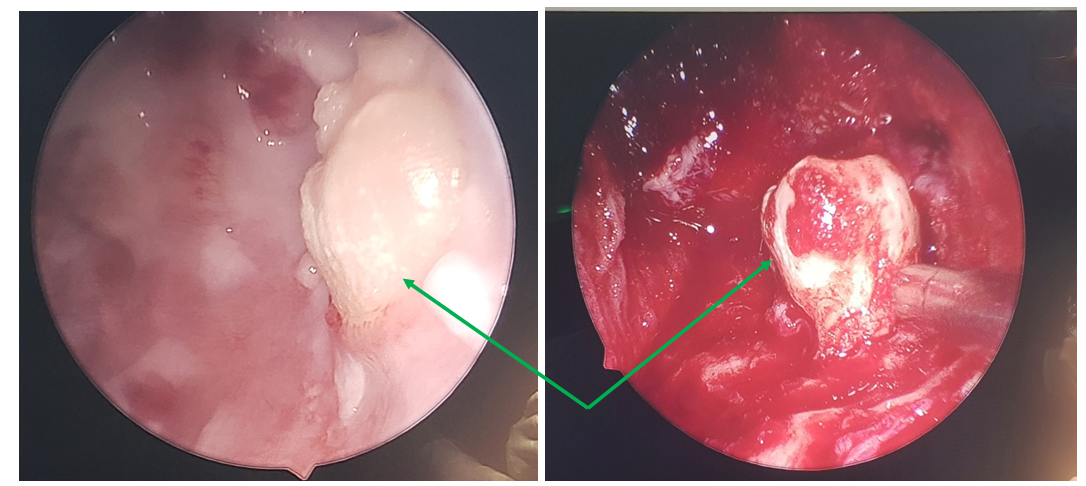

Image of teeth growing underground in the sinuses

The surgery was successfully performed, removing the entire cyst and removing all the hidden teeth in the left maxillary sinus. After the post-operative treatment period, the patient’s current health condition: stable, no stuffy nose, no headaches, no discomfort and very satisfied with the results of the surgery.